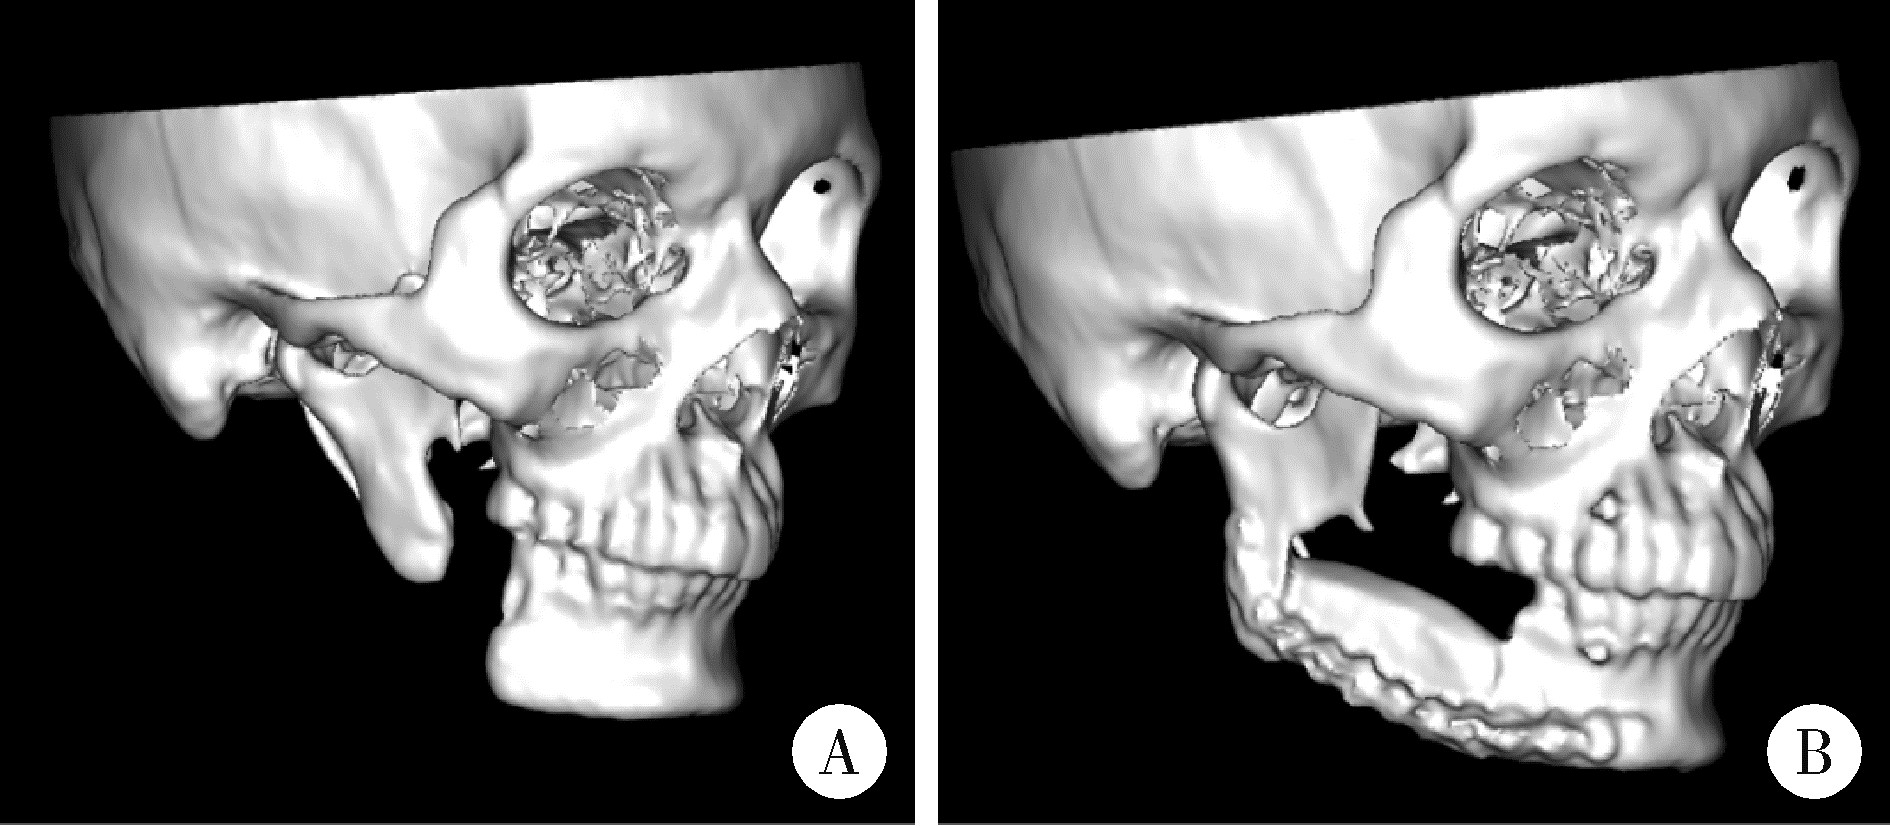

图7

病例5影像资料"

5例患者的信息"

Case No. Gender Age Diagnosis Defect type (according to Jewer classification) Defect area (using FDI system for teeth)

1 Female 46 Fibromyxoma LC 37-41

2 Female 55 Ameloblastoma LCL 33-47

3 Male 25 Ossifying fibroma LC 31-right mandibular angle

4 Male 43 Mandibular defect secondary to resection for ameloblastoma 6 months ago LCL 35-43

5 Male 27 Mandibular defect secondary to resection for keratocyst 2 years ago L 47-right mandibular angle